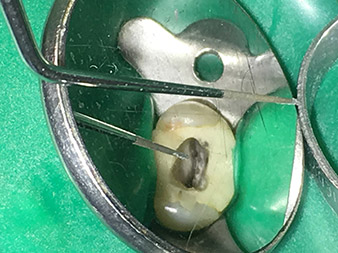

Dr. Nouraie: The use of ultrasonic tips allows targeted, atraumatic, minimal removal of substance at the desired site (e.g., when exposing the canal openings, rounding off the cavity floor and exposing broken-off instruments or posts as well as when processing coronal canal sections).

Canal transitions can be smoothed and rounded off with more precision than when using burs. The activation of the rinsing fluid in particular offers enormous advantages that cannot be guaranteed with other instruments. The special instruments from W&H make it possible to perform completely new indications minimally invasively such as revision of broken-off tips and posts.

Visual aids such as dental loupes or even better a surgical microscope should be employed for all indications in the canal. In addition, I also think it is important that all the applications in the canal – with the exception of the activation of the rinsing fluid – are performed by specialized colleagues with corresponding experience and the necessary expertise in the field.

The risk of perforations and steps forming in the canal must not be underestimated, as the risk increases the deeper one delves into the canal.

Pictures: Dr. Shahrad Nouraie Ashtiani, Bremen